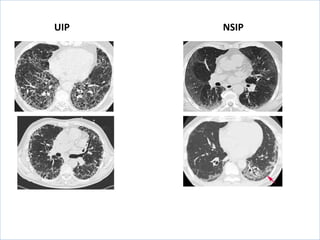

UIP vs NSIP

UIP-like pattern

NSIP-like pattern

Distribution

Honeycombing

Ground glass

Nodules

UIP NSIP

Histology can be UIP or NSIP